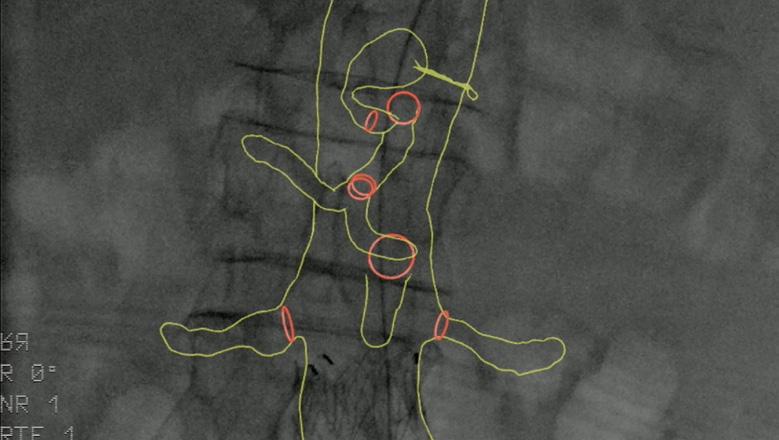

According to Van Herwaarden, electromagnetic tracking addresses the limiting factors of greyscale images, offering instead brightly coloured images, as well as 3D navigation of devices, unlimited viewing angles, and no radiation, with the limited numbers of wires and catheters being a drawback.

Fiber Optic RealShape (FORS) technology from Philips also shows potential in this space, offering the benefits of 3D navigation, unlimited viewing angles, and the radiation-reducing benefits associated with the use of light instead of fluoroscopy, Van Herwaarden highlighted. He noted that one drawback is the fact there are only a limited number of devices available.

Finally, the presenter gave an overview of the pros and cons of image fusion. He stated that there is one system in this space—the Cydar Medical system—that offers automated registration. This technology compares the anatomy visible on live fluoroscopy with anatomy of a preoperative computed tomography angiography

(CTA) and automatically produces 3D overlay, he explained. According to the presenter, this technology offers “a significant reduction of contrast agent and also reduction of procedure time,” despite having a somewhat “complex setup”. Image fusion is “widely available” and, in the presenter’s opinion, “should be used in all complex procedures”.

Van Herwaarden summarised that these technologies show radiation-reducing potential, the small number of available publications suggest that these techniques are “still minimally applied”. According to the presenter, the future of these technologies lies in their combined use. For example, he said that, while electromagnetic tracking and FORS are “still under development,” they do offer “an even greater promise for simplifying complex procedures and realising dose reduction for patients and for staff,” when used in combination with IVUS or a robotic navigation system.